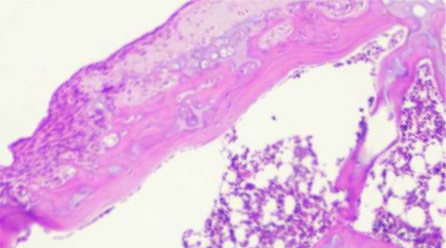

A laboratory study demonstrated that Algyl GGP is significantly more effective in treating knee osteoarthritis than monocomponent hyaluronic acid or saline solution, and leads to the regression of degenerative cartilage changes.⁶

Fig. 3. Group with induced osteoarthritis after application of Algyl GGP: cartilage surface is smooth, indicating ongoing regeneration. Fig. 3. Group with induced osteoarthritis after application of Algyl GGP: cartilage surface is smooth, indicating ongoing regeneration.